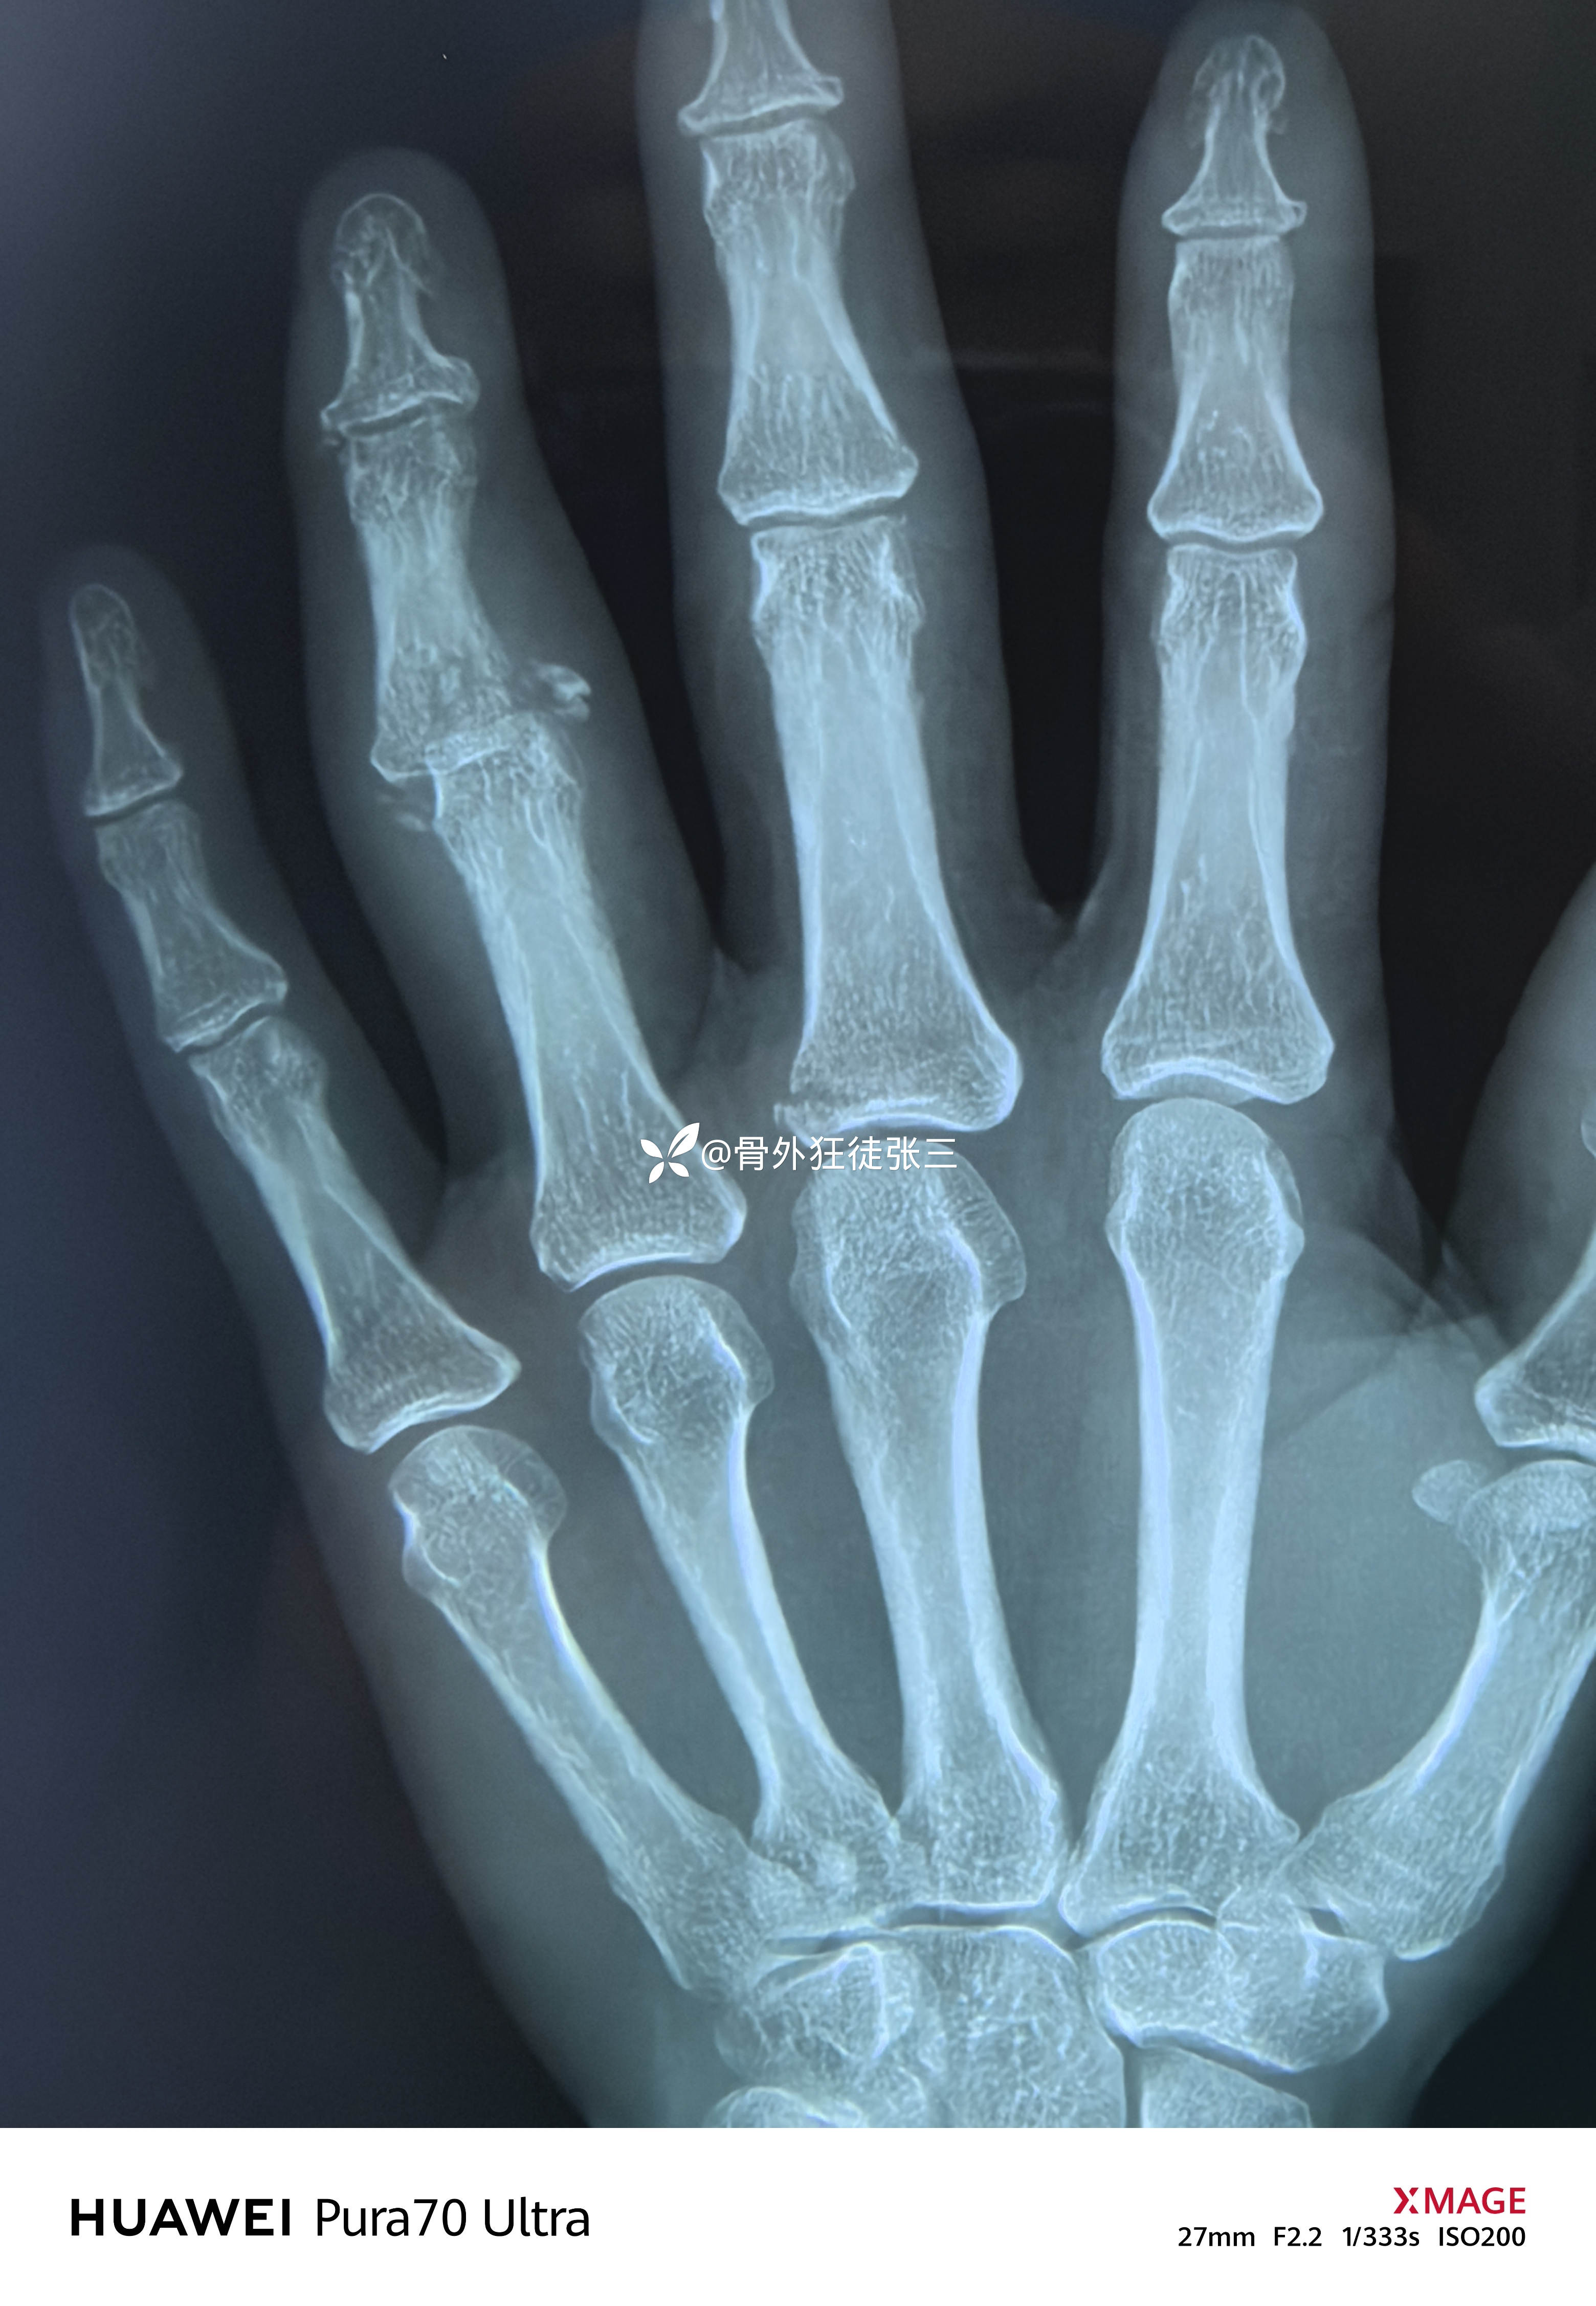

X线显示近指间关节后脱位

中节指骨基底掌侧浅屈肌腱止点骨折

左手环指中节指骨Pilon骨折